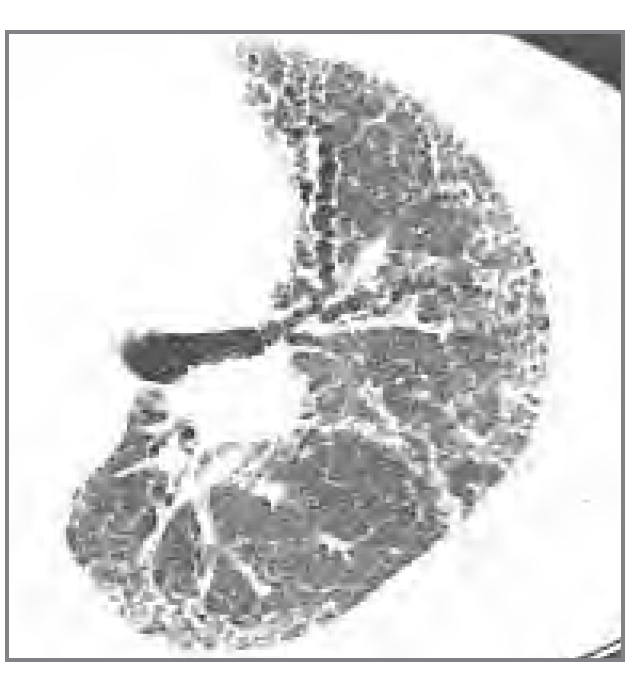

What is this? (what feature is shown?)

UIP (honeycombing?)

What is this? (What feature do we see?)

NSIP (micronodules?)